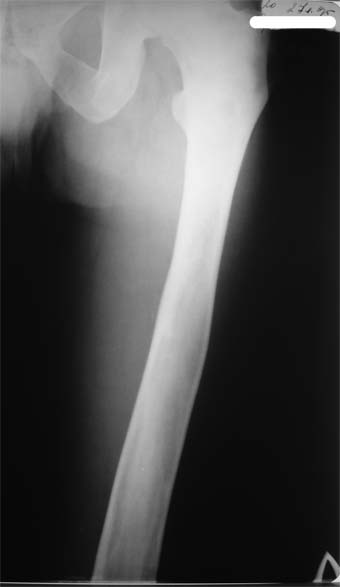

Коллеги!Пациент Д., 35 лет, В 1985 году был поставлен диагноз гемигипоплазия правой нижней конечности. Укорочение 5 см, в 1987 году остеотомия правого бедра, аппарат 4 месяца, удлинили на 2 см из-за нагноения спиц аппарат сняли. В настоящее время Жалобы на дискомфорт, тяжесть в левом бедре, голени при длительной ходьбе, при длительном лежании на левом бедре. Эти жалобы беспокоят втечение 5-6 лет. В 1999 году выявили "изменения" (со слов больного, выписки нет на руках) бедренной кости и костей голени слева. Тогда же предложили в ЦИТО срочно делать какую-то операцию. При осмотре: Правая нижняя конечность. Имеются рубцы на правом бедре по наружной и внутренней поверхностям. Ограничения движений в коленном суставе нет. Кровоснабжение, иннервация сохранены. Левая нижняя конечность. Левое бедро увеличено в объеме, при пальпации пальпируется бедренная кость большего диаметра по сравнению с левым бедром. Пальпация безболезненна. Голень обычной формы. Объем движений в суставах полный. Кровоснабжение, иннервация сохранены. Имеется разница в длине конечностей правая короче на 4-5 см за счет бедра и голени. В приложении вид больного и рентгенограммы бедра 2001 год и 2005 год. Что бы это могло быть? О чем можно думать? Онкология? С уважением Коробушкин Глеб Владимирович Российский государственный медицинский университет кафедра травматологии, ортопедии и ВПХ, доцент

У больного полиоссальноая форма фиброзной дисплазии с поражение левой бедренной и большеберцовой кости. На рентгенограммах - тотальное разрастание и остончение кортикального слоя. Имеется удлинение левой нижней конечности на 2,5-3 см за счет голени. Больному показано оперативное лечение левой большеберцовой кости.